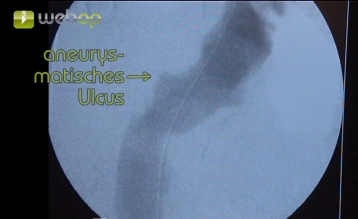

En la contribución se demuestra la exclusión endoluminal de un ulcus ateromatoso penetrante (PAU, excéntrico 32 x 24 mm) de la aorta descendente. Debido a dos operaciones previas de cirugía vascular en la ingle izquierda y arteriosclerosis grave se realiza una exposición extraperitoneal de la A. iliaca externa.

En un diámetro o una profundidad del ulcus de ≥ 20 mm está indicada una atención endovascular electiva. En indicios de una ruptura inminente (dolores, sangre extraaórtica) la atención endovascular es urgente. El dolor se menciona como uno de los criterios principales para un procedimiento operatorio urgente.